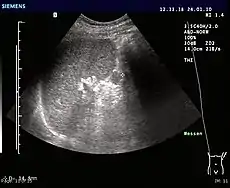

Ultrasonography of an accessory spleen.